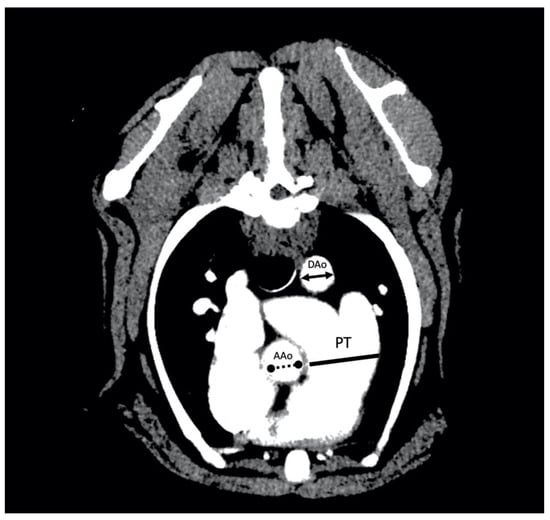

For the evaluation of the PT:Ao ratio, two different measurements were made to obtain the relationship between the PT and the ascending (PT:AAo) and descending (PT:DAo) portions of the aorta. The images of the soft tissue algorithm were used and the ratios were determined following previously established protocols [9,10]. To this aim, the cross-sectional image in which the diameter of the PT was widest was selected. The measurement of the PT was performed by tracing a transverse axis over the widest diameter of the PT, ventrally to the widening and branching in the left and right pulmonary arteries. Furthermore, the dimensions of the short axis of the DAo and the AAo were also measured. The diameters of DAo, AAo and PT were measured on the same image, so that all structures were in the same phase of the cardiac cycle. In all cases, the inner diameters of the vascular lumen was measured, not considering the vascular walls (Figure 1). The DICOM CT images were transferred to a computer and analyzed using an imaging software program (OsirixTM v. 5.6, Geneva, Switzerland). The interobserver variability of PT:Ao image acquisition and PT:DAO/PT:AAo measurement was evaluated separately in 10 dogs by two different cardiologists trained and supervised by a radiology consultant, obtaining comparable values. Measurements for all dogs were performed by a single cardiologist.

Figure 1. Arterial-phase postcontrast transverse thoracic angiogram CT image at the level of the pulmonary trunk (PT) in a 16 kg male beagle with an RPAD index of 17%. The PT to aorta ratio measurement technique consists of the measure of the maximum diameter of the PT measured immediately ventral to the bifurcation into left and right pulmonary arteries (solid line) and the measure of the short axis of the diameter of the descending part of the aorta (DAo) (solid line double arrow) or the short axis of the diameter of the ascending part of the aorta (AAo) (no solid line double arrow). The PT:DAo ratio of this dog was 1.72 and the PT:AAo ratio was 1.47.